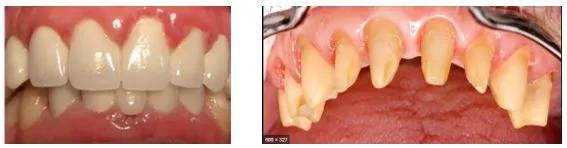

Trước đây, khi bạn đến làm răng sứ, các bạn chỉ đưa hàm răng của mình cho các bác sĩ mài nhưng bạn không hình dung được nó được mài nhỏ cỡ nào, rồi bạn không biết được hàm răng và nụ cười của mình tương lai sẽ ra sao. Và thật đáng buồn khi nụ cười của bạn trở nên xấu đi hay không đẹp như bạn nghĩ, và tệ hơn nó lại gây ra những tai biến khác như nhiễm trùng, hôi miệng, thức ăn giắt kẽ răng… Tất cả mọi thứ đều mơ hồ!

Từ thiết kế này bạn có thể hình dung thấy kết quả sau cùng trước khi làm, giúp bạn nhìn rõ được mức độ điều chỉnh răng của bạn cho mặt dán sứ như thế nào? hay những điều chỉnh cần thiết trước đó để có được hàm răng hoàn hảo như điều chỉnh nướu nếu nướu của bạn chưa đều, hoặc cần niềng răng để chỉnh những răng bị lệch lạc trước khi làm răng sứ/ veneer, tránh bị mài răng.v.v…

Ngoài ra, bản thiết kế đẹp giúp bạn hiểu rõ hơn về nụ cười của chính mình. Nụ cười nó sẽ có tương tác qua lại với tính cách của bạn, do đó bạn nên trình bày về tính cách của bạn để bác sĩ sẽ hướng bạn đến hình dáng nụ cười phù hợp cho bạn , nó sẽ thể hiện chi tiết trong bản thiết kế như trục răng, độ dày, hình dạng răng…

Và cuối cùng, bản thiết kế sẽ giúp cho bác sĩ thực hiện chính xác mức độ mài chỉnh để mang lại cho bạn hàm răng sứ đẹp hoàn hảo và bền lâu.